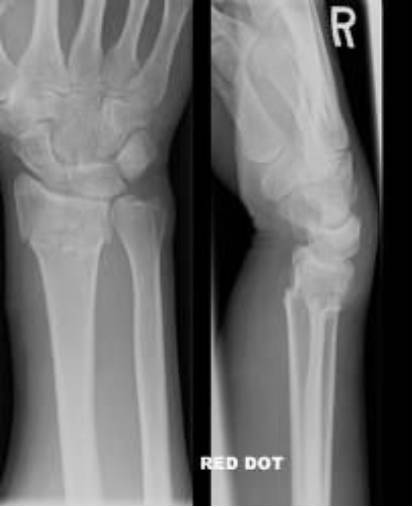

Colles骨折

桡骨远端伸直型骨折,远折端向桡背侧移位。是关节外骨折,常伴有尺骨茎突骨折。